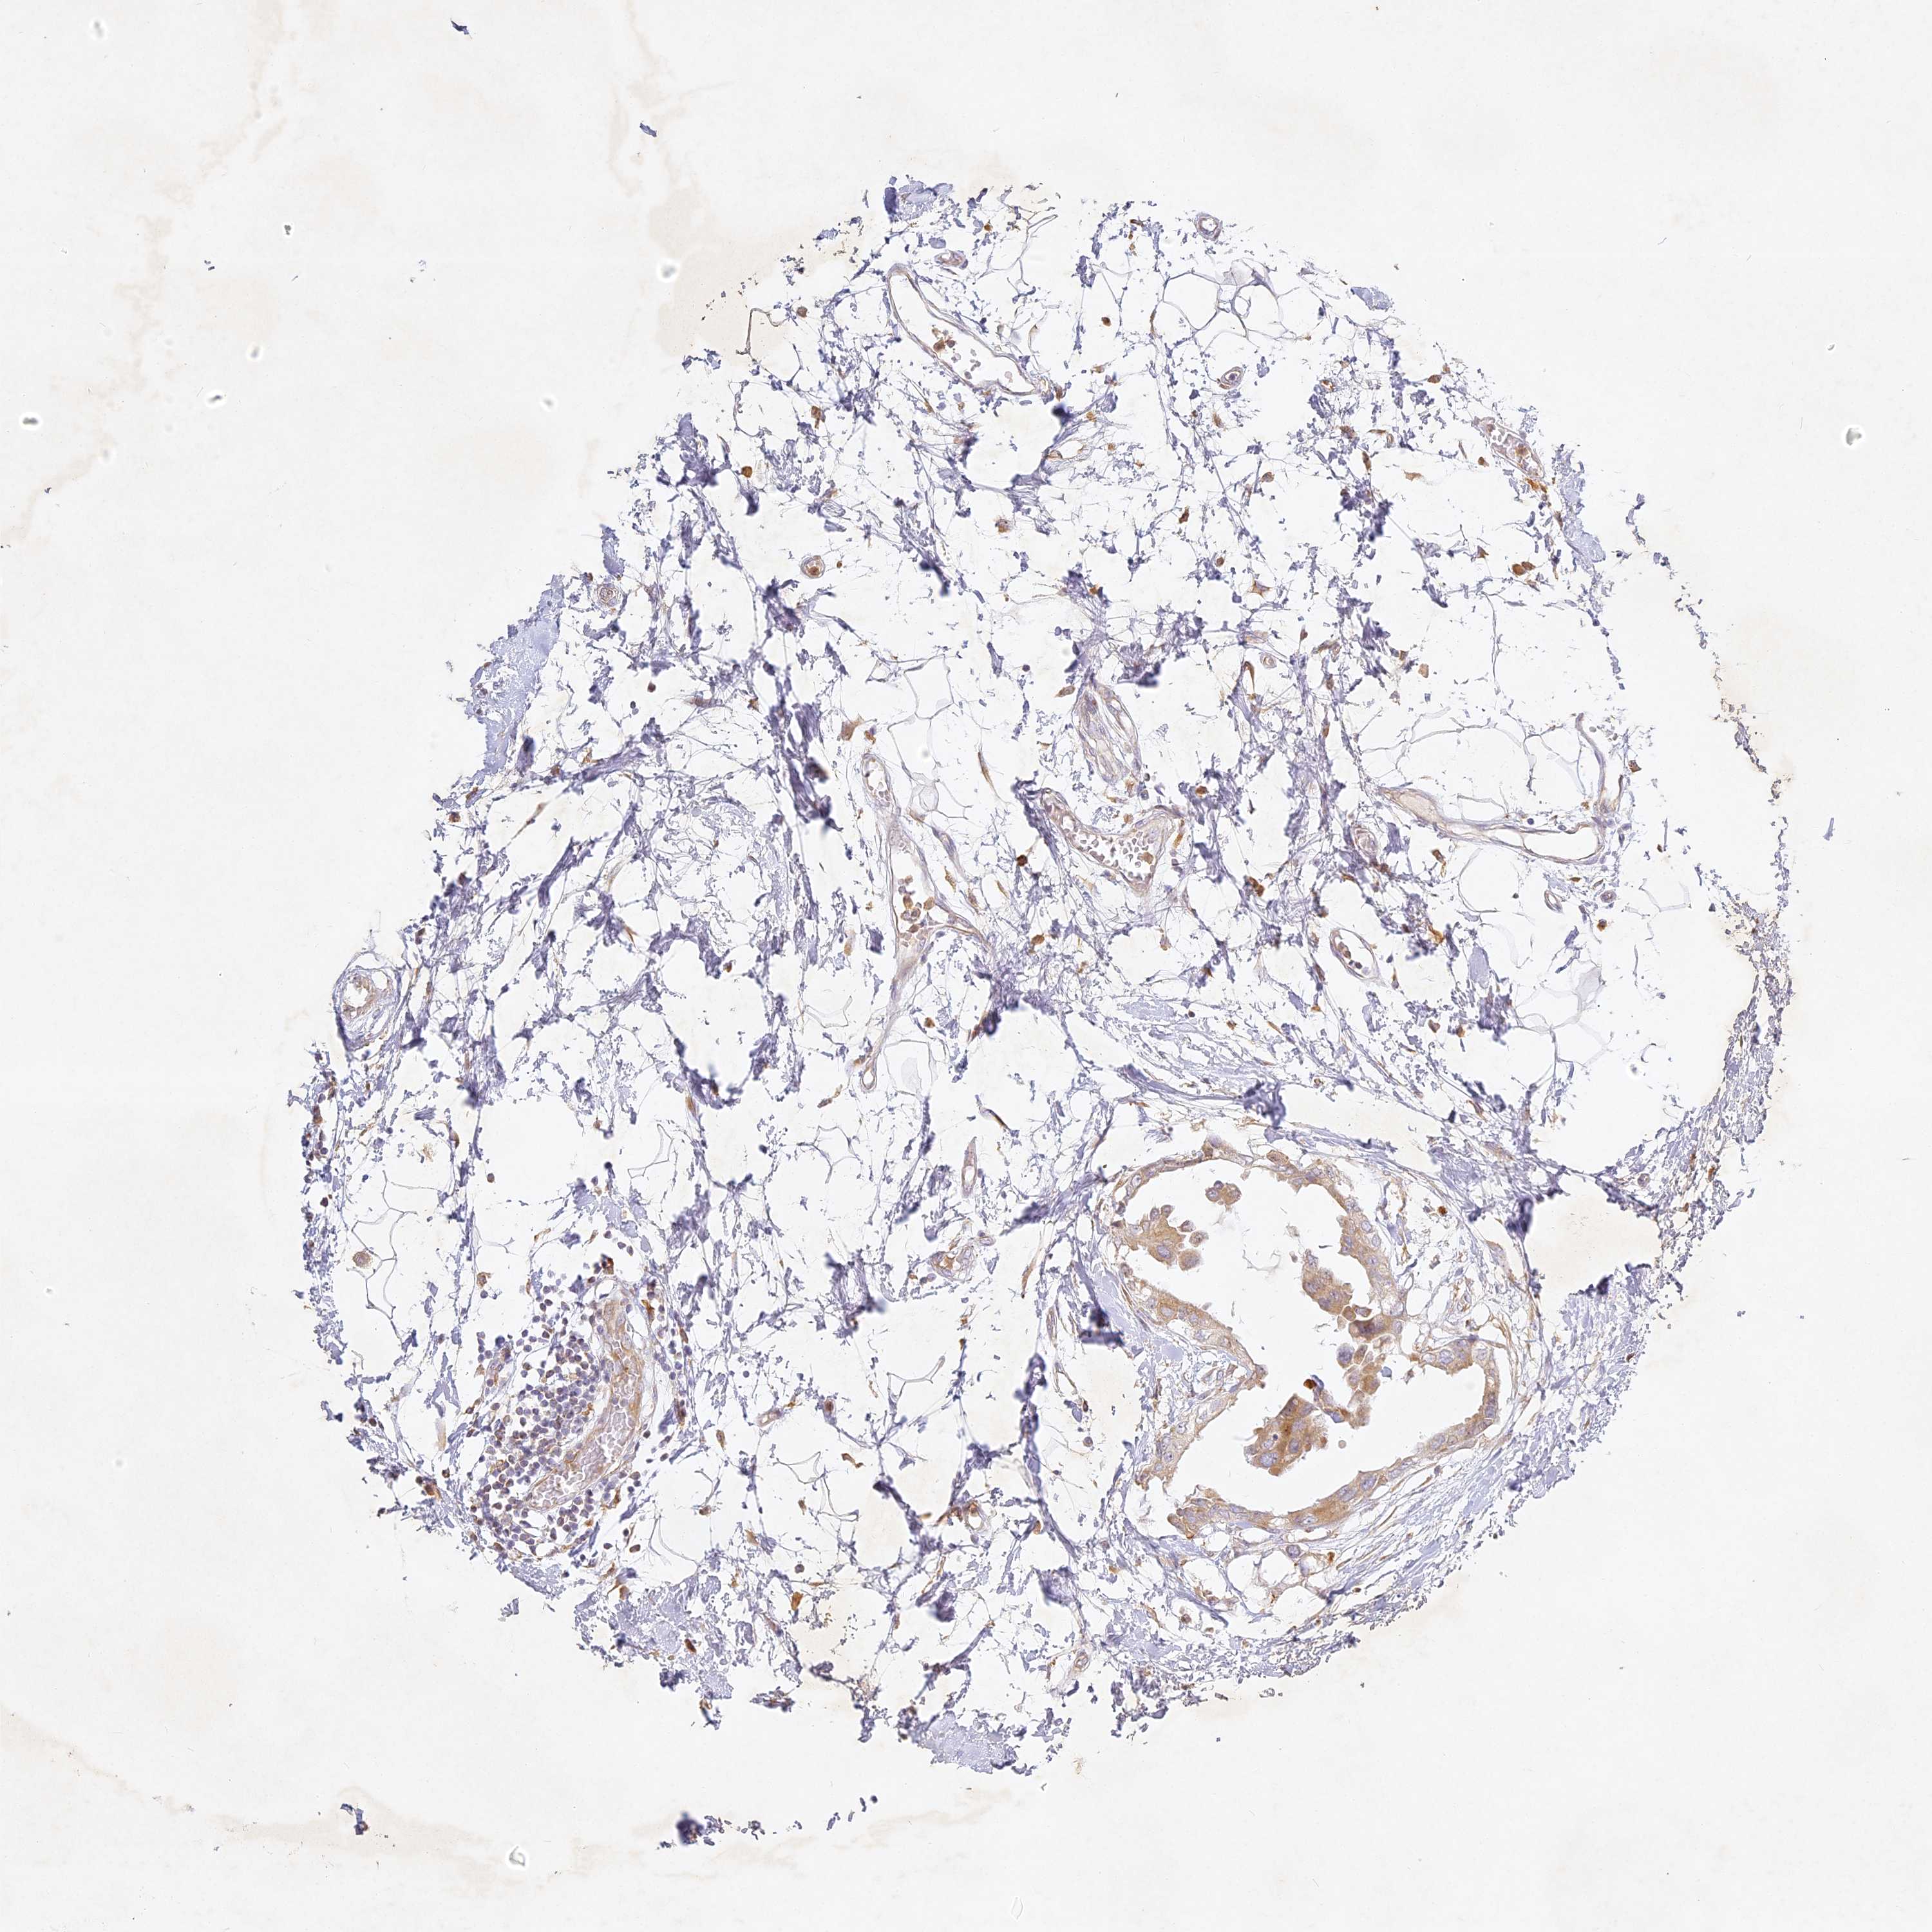

CANCER BREAST CANCER Show tissue menu

BRCA TCGA BRCA VALIDATION PROTEIN EXPRESSION